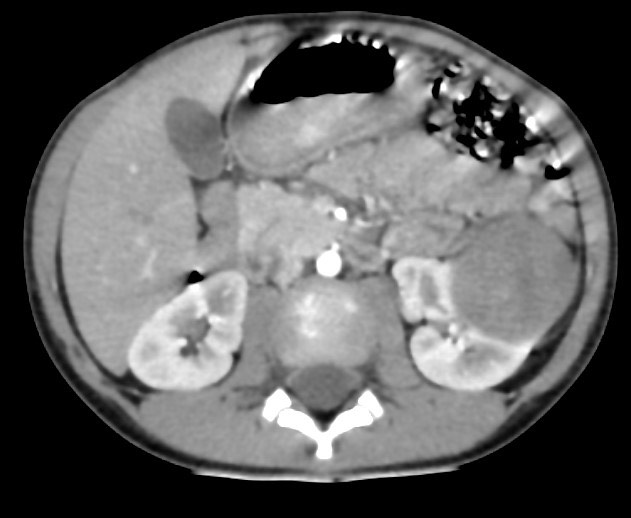

1380. Пациенту 3 лет с жалобами на периодические эпизоды субфебрилитета в вечерние часы, снижение аппетита, без наличия симптомов интоксикации выполнена компьютерная томография патологическим процессом, соответствующим клинико-рентгенологической картине, считают